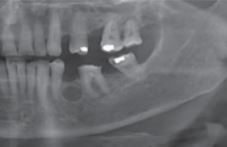

What are the radiological features of a keratocyst?

\* Well defined radiolucency \* Can be unilocular or multilocular \* Typically found in the posterior of the mandible (thinking logically, the 3rd molars are commonly abscent, hence this is why keratocysts could be most commonly found here)